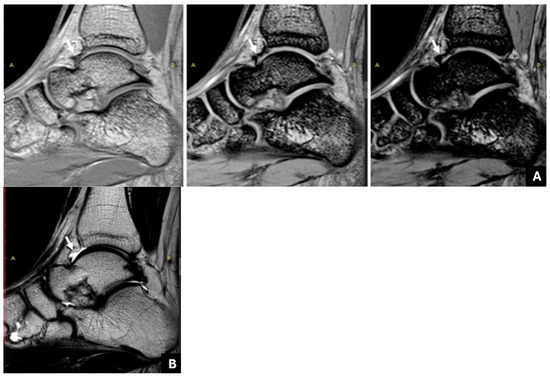

- Akyuz, B.; Polat, A.V.; Ozturk, M.; Aslan, K.; Tomak, L.; Selcuk, M.B. Contribution of 3-T susceptibility-weighted MRI to detection of intraarticular hemosiderin accumulation in patients with hemophilia. AJR 2018, 210, 1141–1147. [Google Scholar] [CrossRef]

- Zhang, L.; Wei, S.; Li, J.; Wang, P.; Ge, Y. Value of 3.0T MRI T2 mapping combined with SWI for the assessment of early lesions in hemophilic arthropathy. Hematology 2022, 27, 1263–1271. [Google Scholar] [CrossRef] [PubMed]

- Prasetyo, M.; Mongan, A.E.; Chozie, N.A.; Prihartono, J.; Setiawan, S.I. Hemosiderin deposition evaluation in hemophilic ankle joints: Association between US finding and gradient-recalled echo MR imaging sequence. Insights Imaging 2021, 12, 107. [Google Scholar] [CrossRef]